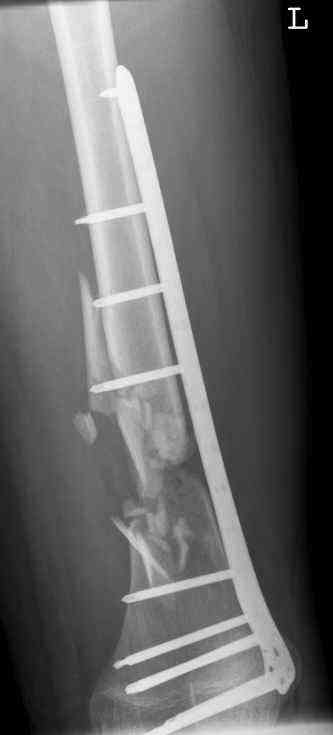

feb 07: retrograde nail + bone graft + BMP

may 07: dynamisation nail

sept 07: locking screw removal (max. dynamisation reached)

nov 07: persistant non-union distal femur; other fractures healed uneventfully.

All with gradual/partial weightbearing etc. Currently 50-100% weight bearing, no pain.

Soft tissues are intact. No smoking or diabetes.CRP <2

What would you do?